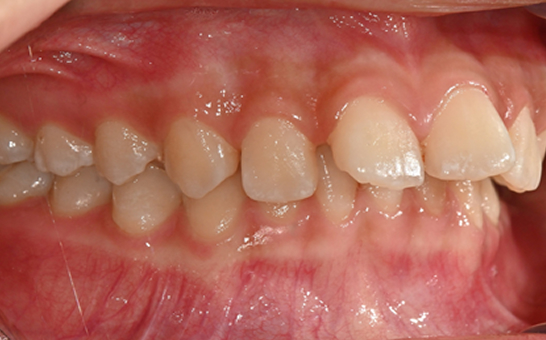

영구치가 나오는 과정에서

공간이 부족한 어린이

앞니의 심한 돌출이나

비대칭으로 인한 기능적

문제가 있는 어린이

턱 성장에 맞춰

치아 교정이 필요한 경우

※ 바른선택치과의원은 의료법을 준수하며 위 케이스는 실제 내원 환자분의 동의하에 공개된 사진과 동일한 환자분께 같은 조건에서 촬영한 사진을 활용했습니다.

개인에 따라 진료 및 치료 방법이 다르게 적용할 수 있으며, 효과와 부작용이 개인마다 다르게 나타날 수 있는 점을 안내해 드리며, 진료 전 전문의료진과 충분한 상담을 권해드립니다.